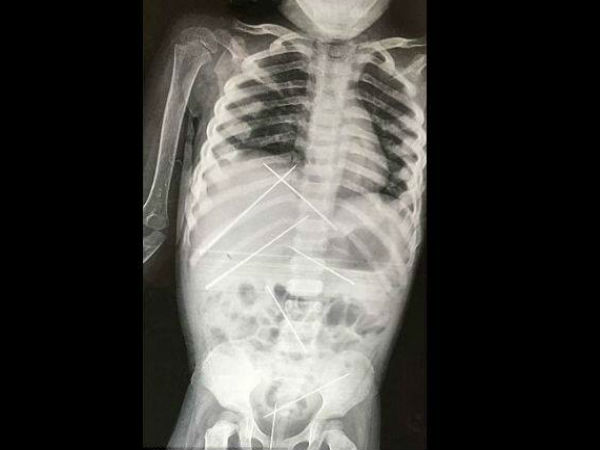

ವೈದ್ಯರು ಈಕೆಯ ದೇಹದ ವಿವಿಧ ಭಾಗಗಳಿಂದ ಏಳು ನಾಲ್ಕಿಂಚು ಉದ್ದ ಸೂಜಿಗಳನ್ನು ಹೊರತೆಗೆದರು. ಇವುಗಳಲ್ಲಿ ಕೆಲವು ಆಕೆಯ ಗುಪ್ತಾಂಗಳಲ್ಲಿಯೂ ಇದ್ದವು. ಎರಡು ಸೂಜಿಗಳು ಯಕೃತ್ ಹಾಗೂ ಮೂತ್ರಕೋಶಗಳನ್ನು ತೂರಿದ್ದರೆ ಒಂದೊಂದು ಮೂತ್ರಪಿಂಡದಲ್ಲಿಯೂ ಒಂದೊಂದು ಸೂಜಿ, ಗುಪ್ತಾಂಗದಲ್ಲೊಂದು ಹಾಗೂ ಕೆಳಹೊಟ್ಟೆಯಲ್ಲಿ ಇನ್ನೊಂದು ಸೂಜಿ ಚುಚ್ಚಲಾಗಿತ್ತು.

ಸೂಜಿಗಳ ಮೂಲಕ ಪ್ರಮುಖ ಅಂಗಗಳು ಘಾಸಿಗೊಂಡಿದ್ದು ಮಾತ್ರವಲ್ಲ, ಈಕೆಯನ್ನು ಆಸ್ಪತ್ರೆಗೆ ಕರೆತಂದಾಗ ಸೂಜಿಗಳಿಂದ ಆಗಮಿಸಿದ್ದ ಸೋಂಕು ಇಡಿಯ ದೇಹವನ್ನು ವ್ಯಾಪಿಸಿಬಿಟ್ಟಿತ್ತು. ಈ ಸೋಂಕುಗಳನ್ನು ತಡೆಯಲು ವೈದ್ಯರು ಇನ್ನಿಲ್ಲದ ಪ್ರಯತ್ನ ಮಾಡಿದರೂ ಚಿಕಿತ್ಸೆಗೆ ಸ್ಪಂದಿಸದೇ ಈ ಬಾಲಕಿ ಕೊನೆಯುಸಿರೆಳೆದಳು.